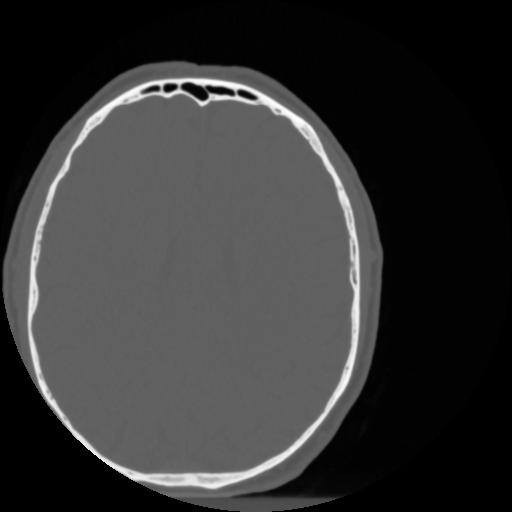

4 CEREBRO,,Vol,0.5,CEREBRO,,